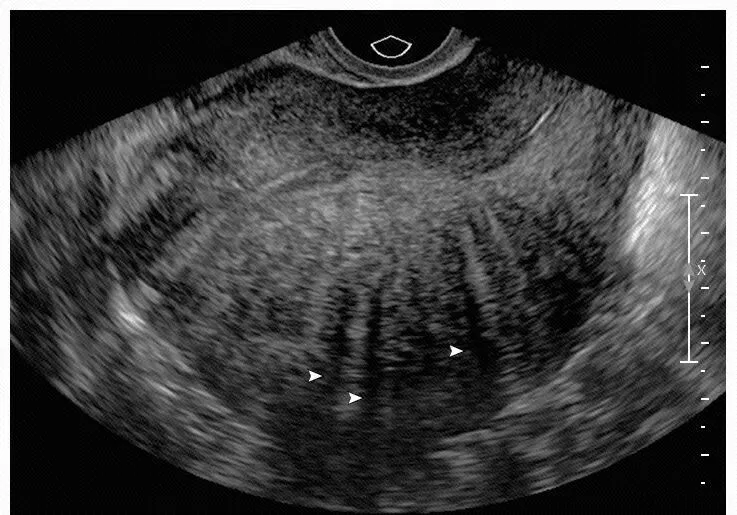

子宫增大,子宫后壁比前壁肌层厚,后壁肌层呈栅栏样改变(箭头示)